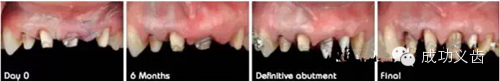

图25.用病例来讲述

图26.从一团糟,到医生的诊断设计

图27.精心的手术

图28.配合多次修整临时牙,达到最终以假乱真的效果。